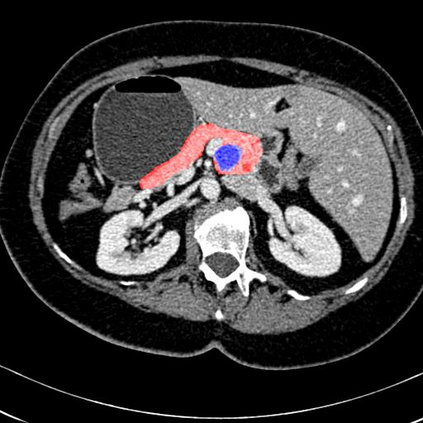

In this paper, we adopt 3D Convolutional Neural Networks to segment volumetric medical images. Although deep neural networks have been proven to be very effective on many 2D vision tasks, it is still challenging to apply them to 3D tasks due to the limited amount of annotated 3D data and limited computational resources. We propose a novel 3D-based coarse-to-fine framework to effectively and efficiently tackle these challenges. The proposed 3D-based framework outperforms the 2D counterpart to a large margin since it can leverage the rich spatial infor- mation along all three axes. We conduct experiments on two datasets which include healthy and pathological pancreases respectively, and achieve the current state-of-the-art in terms of Dice-S{\o}rensen Coefficient (DSC). On the NIH pancreas segmentation dataset, we outperform the previous best by an average of over 2%, and the worst case is improved by 7% to reach almost 70%, which indicates the reliability of our framework in clinical applications.